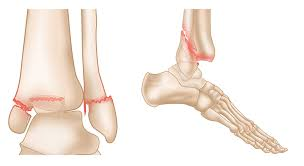

what is a trimalleolar fracture

• Lateral malleolus

• Medial malleolus

• Distal posterior aspect of the tibia, called the posterior malleolus.